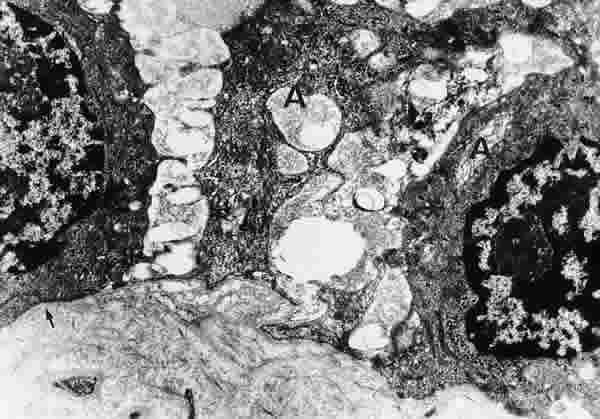

Figura 33

BIOPSIA EN UN PACIENTE CON SS1-GRADO III. LAS CÉLULAS ACINARES (A) ESTÁN MUY SEPARADAS Y ALTERADAS, CON ESCASOS ORGÁNULOS SUBCELULARES, ABUNDANTE CANTIDAD DE MATERIAL FIBRILAR (*) Y CON AUSENCIA DE GRÁNULOS DE SECRECIÓN. EL POLO BASAL DE LAS CÉLULAS ES IRREGULAR. LA MEMBRANA BASAS (FLECHA ARRIBA) ES DISCONTINUA. MICROSCOPIA ELECTRÓNICA. MAGNIFICACIÓN ORIGINAL X8000.